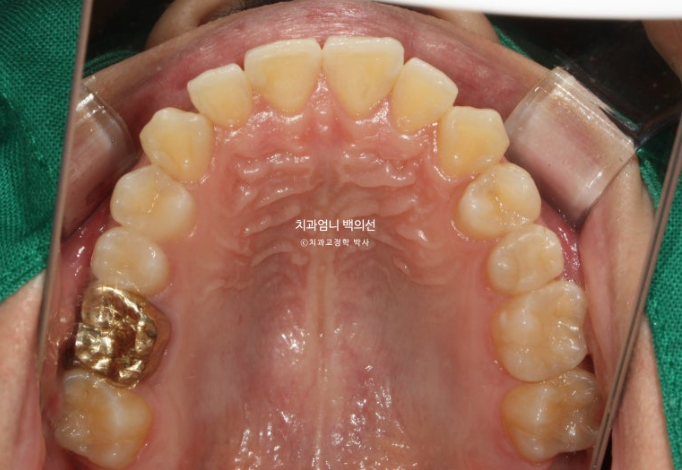

2022.10

송곳니가 많이 회전되어있고

송곳니를 포함한 앞니 치아들이 겹쳐져 있습니다.